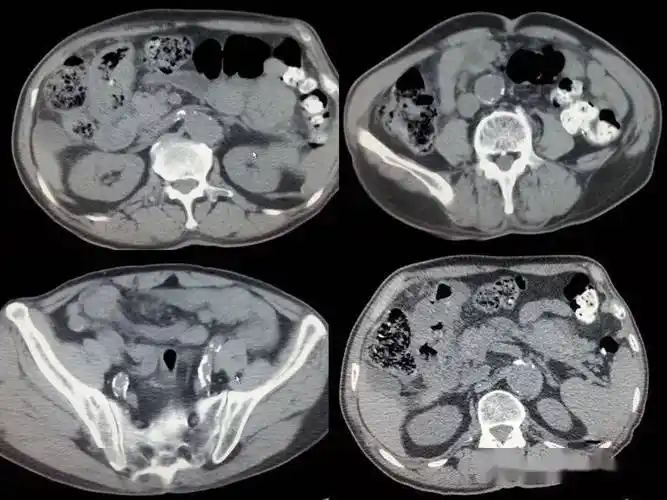

消化道穿孔ct影像大汇总看完印象深刻

5cm的穿孔,全腹腔内积聚大量黄色脓液,感染导致弥漫性腹膜炎,大爷病情